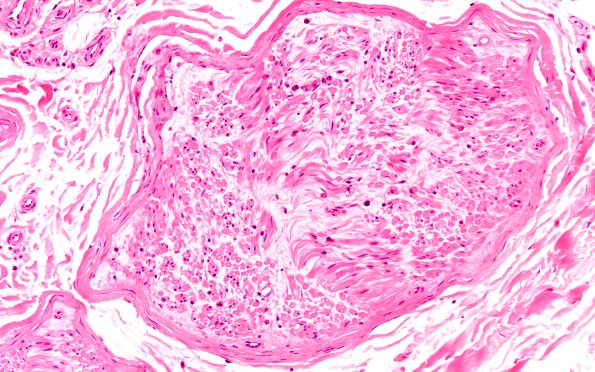

Individual fascicles are often pale reflecting the overall loss of myelin and myelinated axons. (H&E)